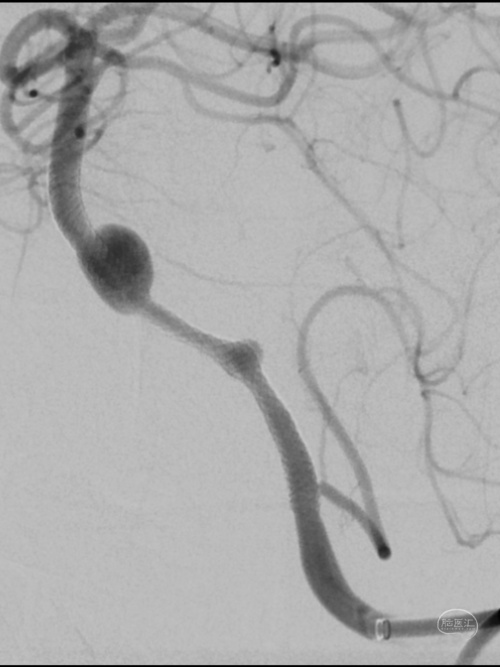

DSA:

3D重建显示基底动脉下部、双椎结合部、左椎多发夹层动脉瘤:

术后造影显示动脉瘤内造影剂滞留明显,载瘤动脉通畅。